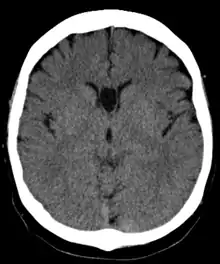

Cave of septum pellucidum seen on CT

The cave of septum pellucidum (CSP), cavum septi pellucidi, or cavity of septum pellucidum is a slit-like space in the septum pellucidum that is present in fetuses but usually fuses during infancy. The septum pellucidum is a thin, laminated translucent vertical membrane in the midline of the brain separating the anterior horns of the right and left ventricles. It lies posterior to the corpus callosum. Persistence of the cave of septum pellucidum after infancy has been loosely associated with neural maldevelopment and several mental disorders that correlate with decreased brain tissue.[1][2][3][4][5]

There are individual differences in the degree of CSP; whereas some have complete closure of the cavum, others present with a small degree (4–6 mm wide, in the coronal plane) of incomplete closure.[4] The most common type of CSP is noncommunicating; that is, it does not connect to the brain's ventricular system. Because of this lack of communication, the previous use of the term "fifth ventricle" is no longer used, and the fifth ventricle is the name often used for the terminal ventricle.